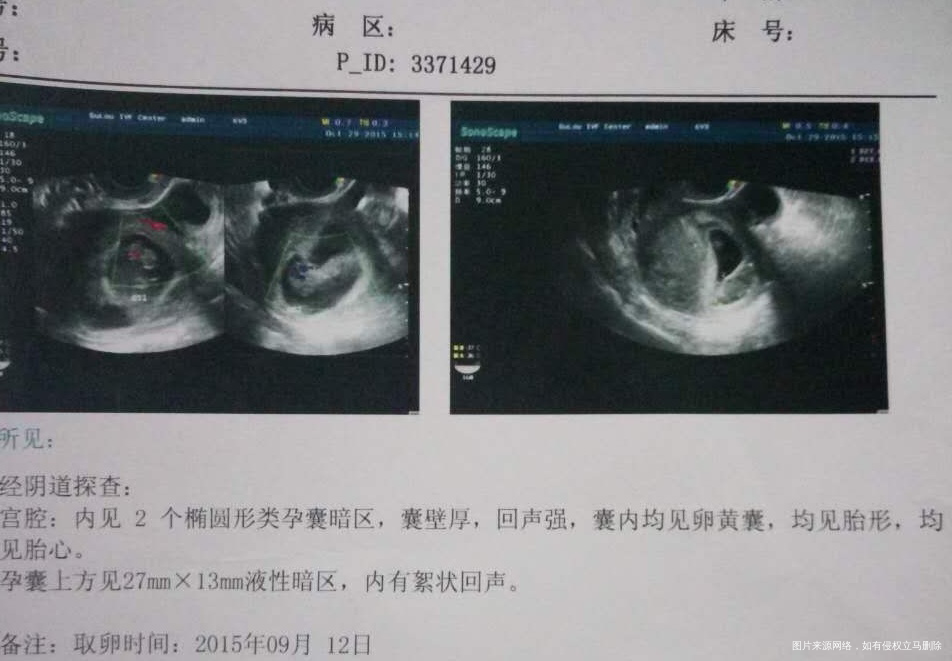

虽然一路上也遇到了困难。腹水见红宫腔有积液。但是宝宝很坚强在一点点的变好。我们一家有四口了。